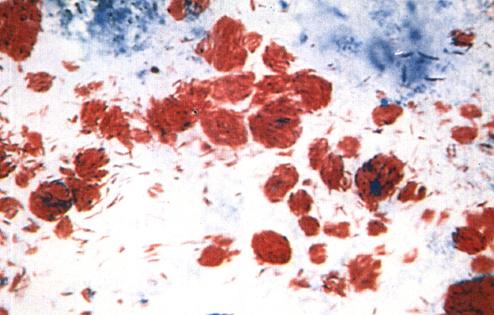

一、麻风杆菌的一般特征(图1-1a)

图1-1(a)

ML经萋-尼氏(Ziehl-Neelsen)抗酸染色法(简称Z-N法)染色在光学显微镜下可看到菌体被染成红色,呈直或略弯曲的杆菌,长1~8微米,宽0.3~0.4微米。ML无鞭毛、无芽孢,至于有无荚膜的问题,至今仍有争论